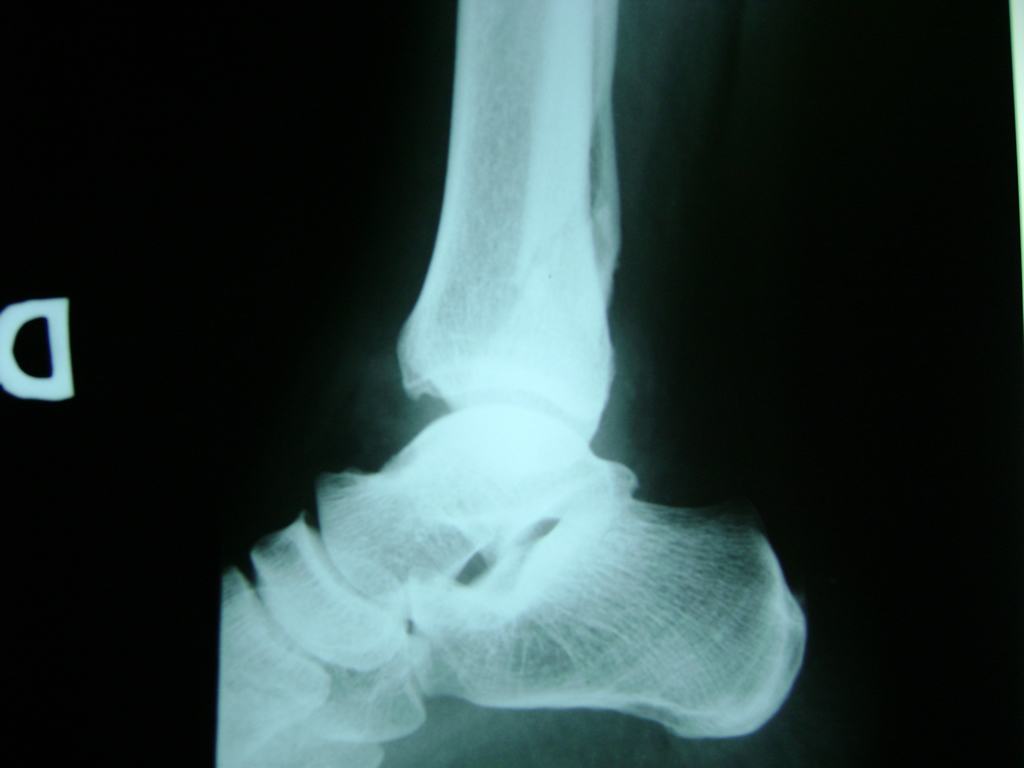

Una fractura de tobillo es la rotura de uno o más de los huesos del tobillo. Estas fracturas pueden ser:

- Los extremos de los huesos están desalineados entre sí (desplazados).

- La fractura se extiende hasta la articulación del tobillo (fractura intra-articular).